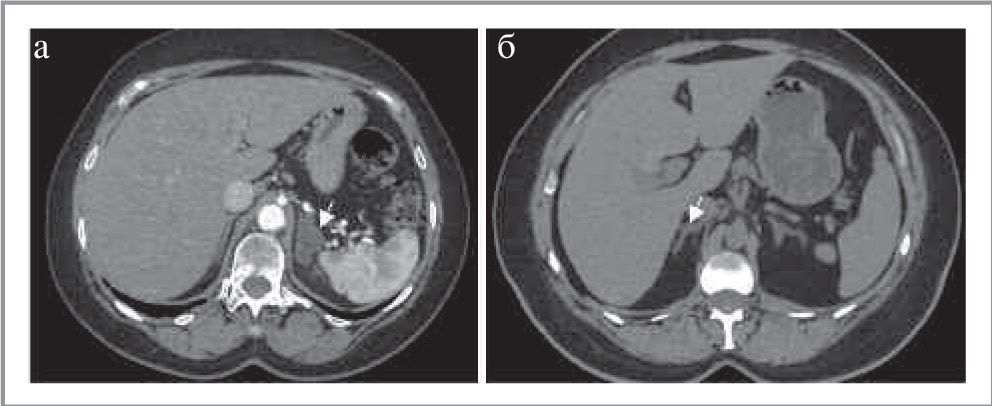

Миелолипома представляет собой доброкачественное образование надпочечника, состоящее из макроструктурных жировых включений и гемопоэтической ткани. Первоначально она описана E. Gierke в 1905 г. C. Oberling в 1929 г. назвал ее «миелолипоматозным образованием». Обычно это образования размерами от нескольких миллиметров до 4 см с четкими ровными контурами, неоднородной структуры. Для них характерно наличие тонкой псевдокапсулы, возможны обызвествления, обусловленные последствиями кровоизлияний, которые обнаруживаются в 27% случаев [13].

Наличие макроструктурного жира (плотность от -30 до -100 ед. Н) является ключевым признаком в диагностике данного образования [14]. При этом количество жировой и гемопоэтической ткани вариабельно (рис. 4). Обычно миелолипомы асимптомны и являются случайной находкой. Однако возможно появление клинических симптомов при кровоизлиянии или компрессии образованием большого размера прилежащих органов. При КТ-диагностике возможна установка ложноположительного диагноза, так как в редких случаях аденома, АКР и феохромоцитома могут иметь включения макроструктурного жира (рис. 5) [15, 16]. Установка ложноотрицательного диагноза возможна при незначительном количестве жира и преобладании гемопоэтической ткани в опухоли. Кроме того, подобную структуру может иметь и липосаркома, поэтому в случае быстрого увеличения размеров и изменения структуры образования при динамическом КТ-исследовании, а также появления признаков инвазивного роста необходимо заподозрить данное заболевание и выполнить пункционную биопсию с дальнейшим морфологическим исследованием [13].

Рис. 4. МСКТ, аксиальная проекция. Миелолипома правого надпочечника (стрелка). КТ-изображения в аксиальной проекции: а – НФ; б – АФ; в – ВФ; г – ОФ.

Рис. 5. МСКТ, аксиальная проекция. Аденома с признаками липоматозной дистрофии.